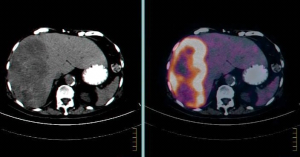

PET-CT הוא כלי חשוב לברור גרורות בכבד מכיוון שמרביתן קולטות FDG, קליטה שהיא אבחנתית לתהליך שאתי בכבד (תצלום 38.10). ה- PET עוזר גם בהגדרת מרחב המחלה בכבד. כל חולה המועמד לכריתת כבד צריך לעבור בדיקת CT תלת פאזי ו- PET-CT להערכת נגעים בכבד ולחיפוש נגעים מחוץ לכבד. רגישות ה- PET-CT היא כ- 90% והדיוק כ- 85%. כימותרפיה טרום ניתוחית מורידה את רגישות בדיקת ה- PET באופן משמעותי.

| תצלום 38.10: שני תצלומים משמאל - ב- CT נראה פגם מילוי בכבד. שני תצלומים מימין - הפגם "נצבע" על ידי FDG ממצא המעיד על תהליך פתולוגי בכבד. | |

|---|---|